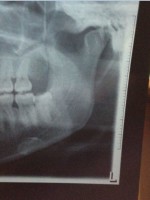

第六位:我不接受X光检查,因为没有需要,又有辐射。

通过X片可以了解到蛀牙的范围、牙痛的原因及镶牙、种植牙的条件是否足够等,因此在诊治过程中,拍片是必要的。依照目前国际放射防护委员会推荐,民众辐射限值每人每年不得超过5毫西弗(msv)=5000微毫西弗,依此计算,每人每年可以接受200张的牙科口内X光照相,所以牙科X光检查剂量是非常低的。